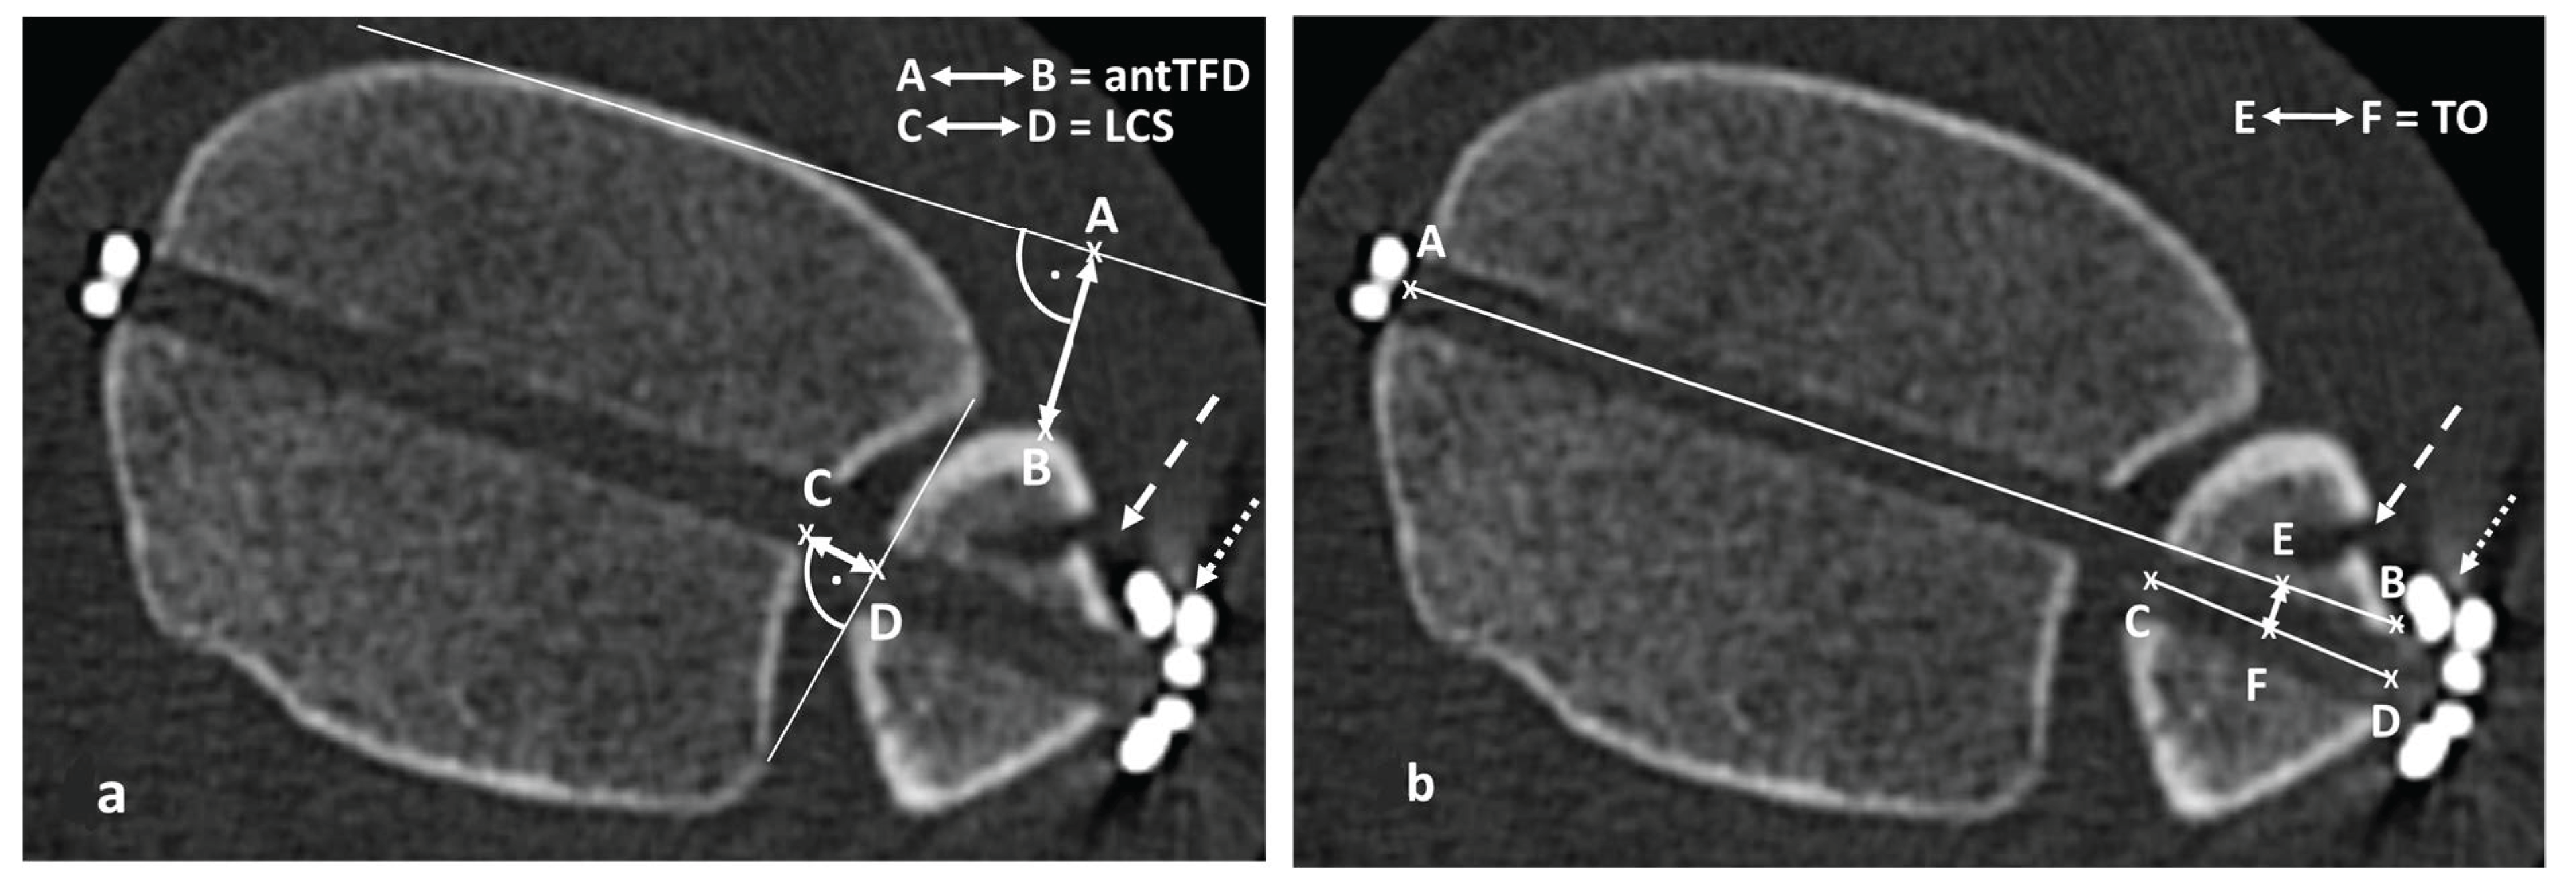

3.2. Parameters Describing the Anatomy of the DTFJ

| Parameter Assessing DTFJ | All N = 44 | Range Min–Max | Female N = 21 | Male N = 23 | p |

|---|---|---|---|---|---|

| DI in mm (SD) | 3.8 (1.2) | 1.3–7.2 | 3.3 (1.2) | 4.3 (1.1) | 0.003 1 |

| LCS in mm (SD) | 3.5 (1.1) | 1.2–5.8 | 3.4 (1.2) | 3.6 (1.1) | 0.378 1 |

| FE in mm (SD) | 0.4 (1.4) | −2.6–3.6 | 0.1 (1.3) | 0.7 (1.4) | 0.196 1 |

| ROI in degrees (SD) | 96 (4) | 85–109 | 96 (4) | 96 (4) | 0.878 1 |

| NTDA in degrees (SD) | 8 (5) | −2–18 | 8 (6) | 8 (4) | 0.672 1 |

| antTFD in mm (SD) | 11.2 (2.8) | 4.4–18.7 | 10.8 (2.2) | 11.7 (3.3) | 0.244 1 |